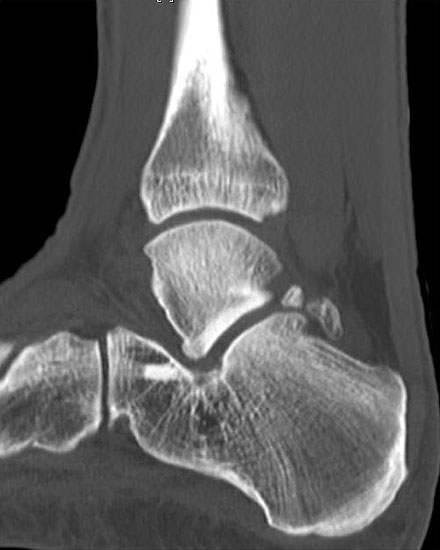

Abbildung Nr. 23 und 24, Video Nr. 4

Große osteophytäre Anbauten, welche die FHL-Sehne vollständig ummauern, sind ebenfalls sehr gut in der beschriebenen Technik adressierbar. Präoperatives CT und intraoperative Bildwandlerkontrolle im seitlichen Strahlengang (linke Seite).